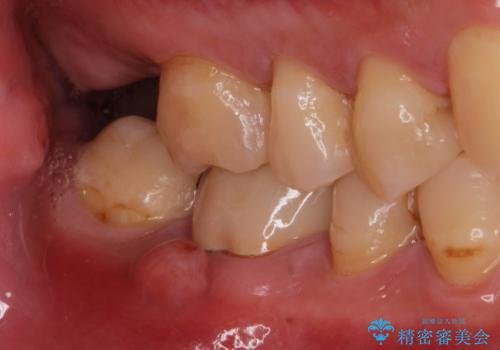

歯茎が腫れた。ジルコニアクラウンやりかえ。

- メンテナンスで来院された患者様です。

歯茎が腫れたとの事で歯の神経が失活していたので精密根管治療を行い、ジルコニアクラウンで治療を行いました。

神経が失活しているので痛みは感じにくいですがこのまま放置をしてしまうと骨が溶けたり痛みが出たりします。

このように歯茎にニキビみたいな物が出た場合、あるいは存在する場合すぐに歯科医院に相談することをおすすめします。